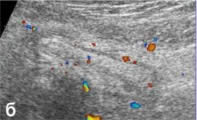

б, д - продольное и поперечное сканирование

(соответственно) визуализируемого фрагмента червеобразного

отростка в режиме дуплексного допплеровского сканирования.

Прослеживается сосудистый рисунок в стенке отростка. |

б - ДДС в энергетическом режиме. Определяется гиперемия

червеобразного отростка (поперечный срез). |

| в - ДДС в цветовом режиме, определяется гиперемия стенки

червеобразного отростка (поперечный срез), лежащего рядом

с подвздошными сосудами. |